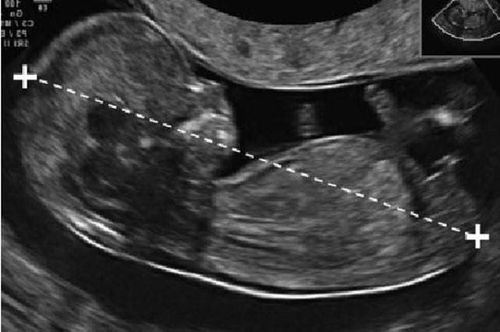

Chào Bác sĩ. Thai của em được 12 tuần tuổi, độ mờ da gáy là 7,5, tim khá bất thường, tràn dịch màng phổi. Em được bác sĩ khuyên nên bỏ thai. Em rất hoang mang và đau khổ. Em nên làm gì trong tình huống này ạ? Mong sớm có câu trả lời từ bác sĩ. Cảm ơn Bác sĩ.